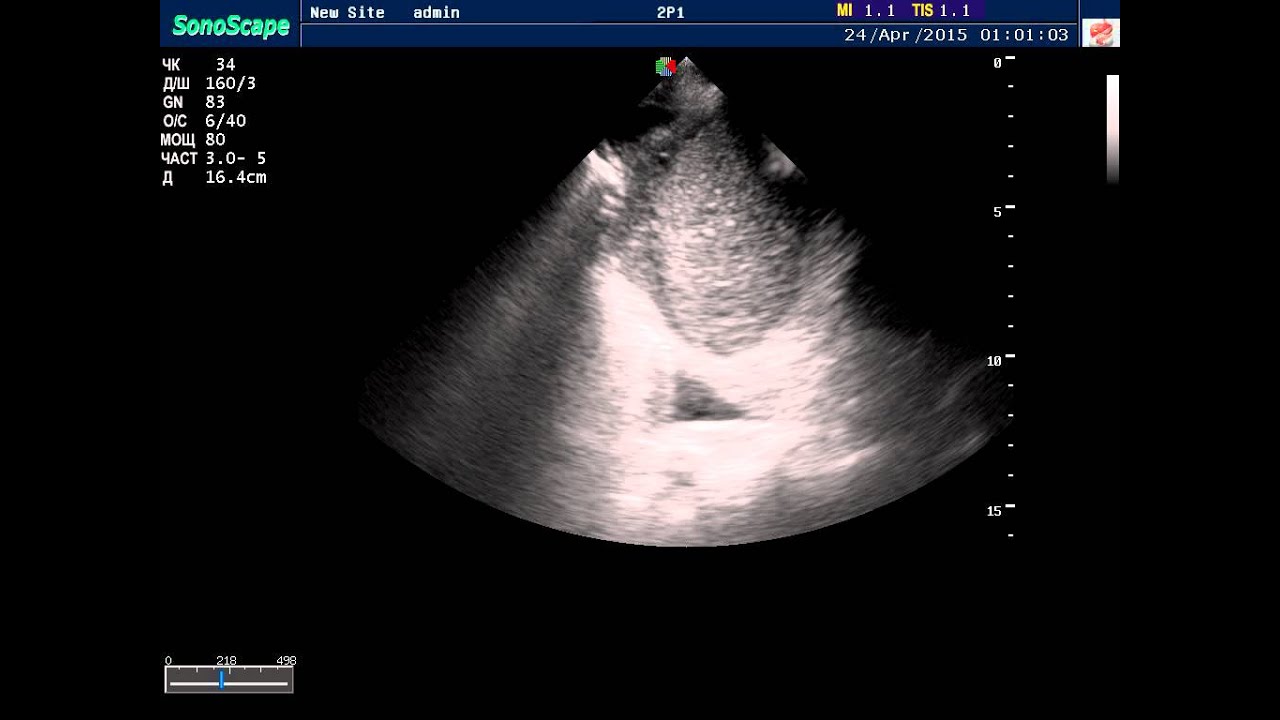

Пучкова узи

Пучкова узи 84 фотографий